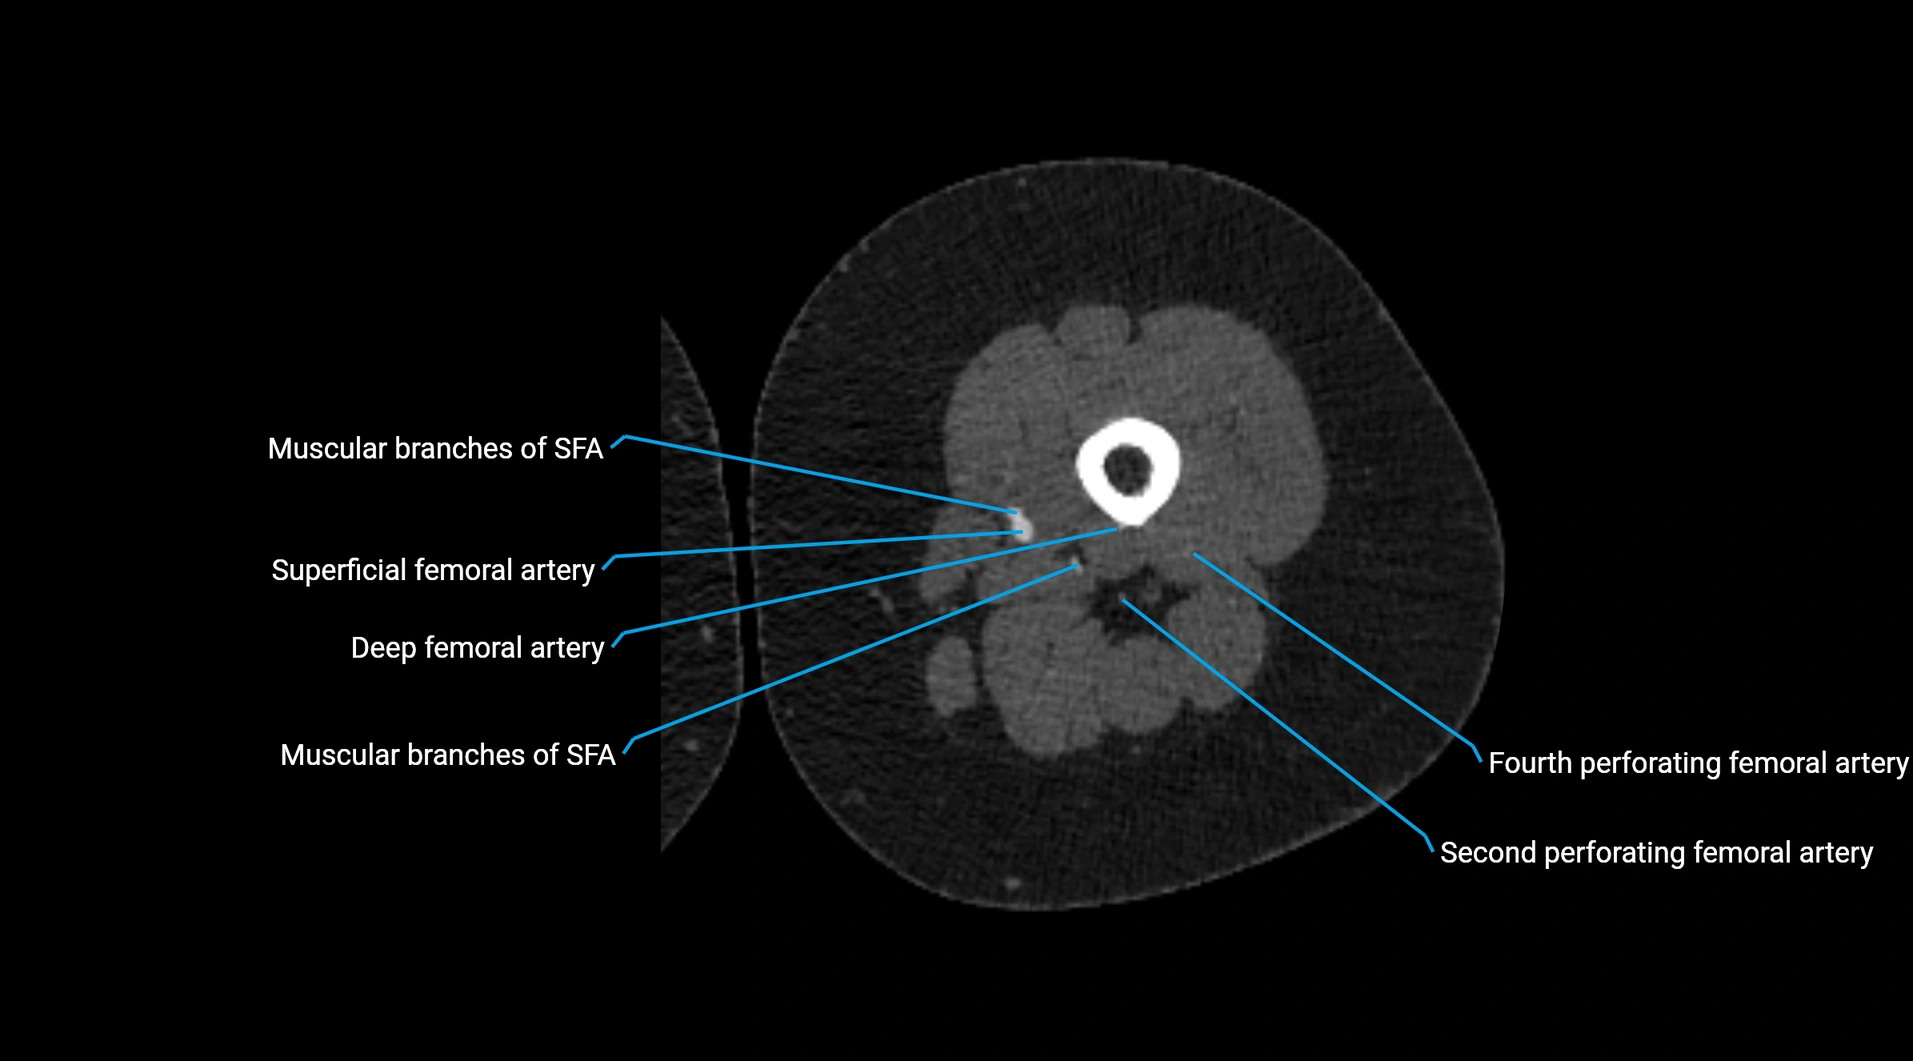

CT images

image

Contrast-enhanced CT (CTA):

• Gold standard for abdominal aortic imaging

• Provides excellent detail of lumen, wall, aneurysm, thrombus, and branch vessels

• Multiplanar and 3D reconstructions help in aneurysm measurement, stent graft planning, and dissection evaluation